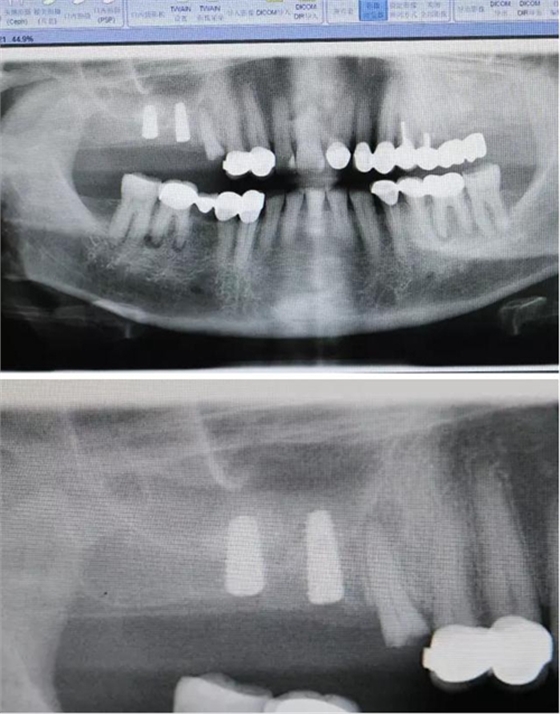

北京種植牙醫(yī)聯(lián)盟特聘講師原解放軍272醫(yī)院口腔科主任2000年開展種植牙專業(yè),年種植量1000顆以上;韓國DIO種植系統(tǒng)外科培訓(xùn)講師;韓國DENTIS種植系統(tǒng)外科培訓(xùn)講師;韓國DIO系統(tǒng)、DENTIS系統(tǒng);種植后上部結(jié)構(gòu)修復(fù)指導(dǎo)老師;北京種植牙醫(yī)聯(lián)盟理事長;國際種植牙醫(yī)協(xié)會(huì)(ICOI)會(huì)員。